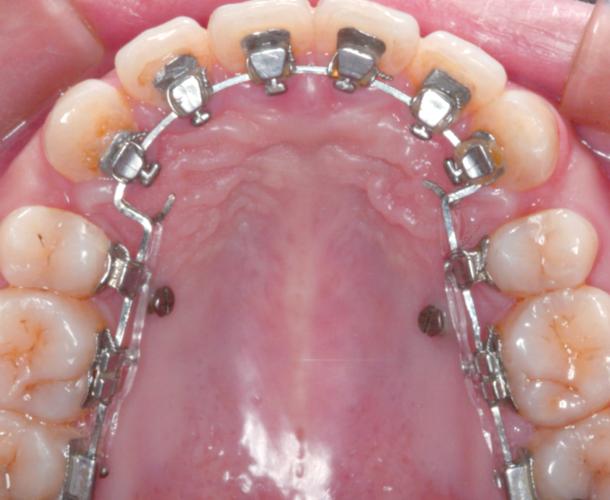

托槽定位与粘接:三维控制精准度

托槽定位需遵循“三维控制”原则,确保牙齿在近远中、唇舌向、垂直向的准确移动,以固定矫治器为例:

- 垂直向定位:参考临床冠高度(CCV),如上颌中切牙CCV为4.5mm,托槽槽沟底缘距切缘2/3 CCV处;下颌第一磨牙托槽距牙合面4.5mm。

- 近远中定位:托槽中心与牙冠中心对齐,避免偏移导致牙齿扭转。

- 唇舌向定位:根据牙齿轴倾度调整托槽底板角度,如上颌中切牙轴倾度5°-10°,托槽底板需相应倾斜。

定位后,用镊子夹持托槽,对准牙面轻压,挤出多余粘接剂,用探针去除边缘溢出物,避免刺激牙龈,最后光照固化:每颗牙光照40秒(近中、远中、龈方、切方各10秒),确保粘接剂完全聚合。